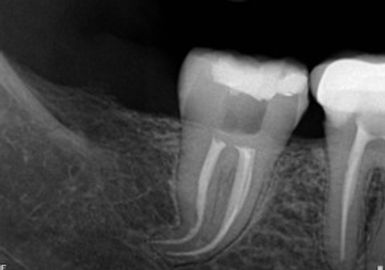

Kanal tedavisi tekrarı nedir?( Retreatment )

Steril koşullarda ve doğru yapılmış kanal tedavilerinin başarı oranı %90 – 95 arasındadır. Tedavi sırasında temizlenmeyen sinir dokusu kaldıysa, kök kanal dolgusunun ve üst dolgusunun yeterli yapılmadığı durumlarda kanal içerisine mikroorganizmaların sızmasıyla, tedavi sırasında perforasyon ya da kırıkların oluşmasıyla,travma veya çürük nedeni ile kanal içine yapılan dolgu tükürük ile uzun süre temas etti ise kök kanal tedavisinin tekrarı gerekir. Başarısız bir kanal tedavisini yemek sırasında dişlerde ağrı, sponton ağrı, kök ucunda şişlik ve kızarıklık belirtilerinden anlayabiliriz. Başarısız kanal tedavisi yenilenerek, tedavi tekrarlanır. Bu işlem yetersiz kalıyorsa apikal rezeksiyon işlemi uygulanarak, kök ucuna cerrahi olarak ulaşılır, enfeksiyon temizlenir ve kapatılır. Kanal tedavisi tekrarlanması ve cerrahi müdahele yetersiz kalırsa dişin çekimi gerekebilir.

✔️ Kanal yenileme (Retreatment) nedir?

Önceden kanal tedavisi yapılmış bir dişin yeniden tedavi edilmesidir.